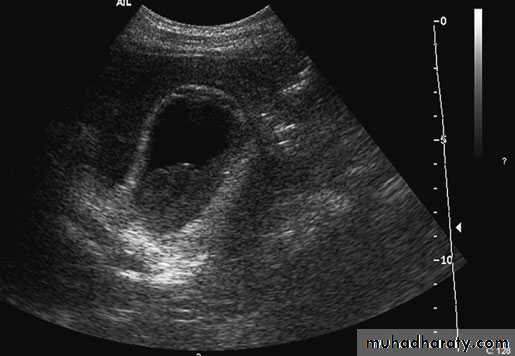

62Cholecystitis. Ultrasound demonstrates pericholecysticfluid (thin arrow), gall bladder wall (thick arrow) and biliary sludge